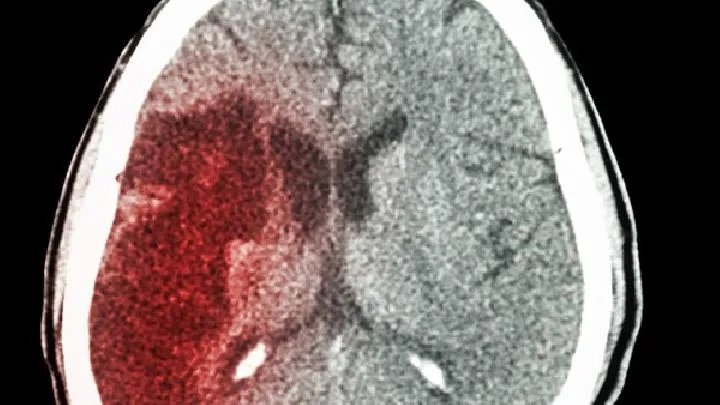

此外,线粒体的峰值可以是板层或同心圆,后者看起来像“年轮”状态。大脑的基本病理变化为海绵状脑组织、神经元退行性变、灶性坏死、星形胶质细胞增生、继发性髓鞘脱失和基底核铁沉积。